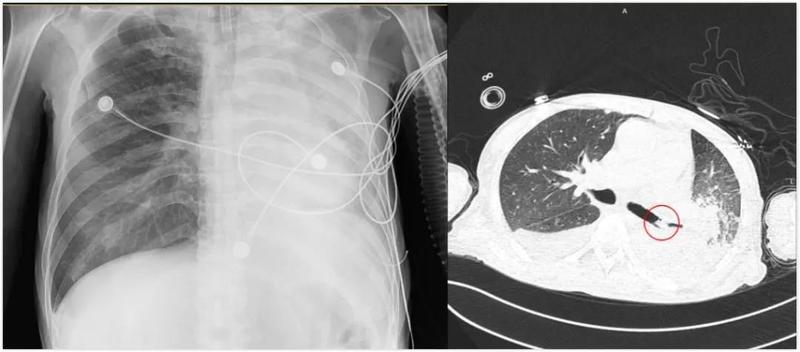

氣胸和肺不張都是肺部常見病,分辨二者很重要,對(duì)治療意義重大

人體的肺外面包裹著兩層膜,內(nèi)層是臟層胸膜,外層是壁層胸膜,兩層胸膜形成一個(gè)完整密閉的腔,即胸膜腔。氣胸是由于胸膜腔完整性受到破壞,氣體進(jìn)入腔內(nèi),氣胸可壓縮肺部形成肺不張。肺不張是由于腫瘤、異物或外壓導(dǎo)致氣道狹窄或者肺被壓縮,從而引起遠(yuǎn)端的肺萎陷,含氣量減少,這種狀況就稱為肺不張。氣胸與肺不張?jiān)谟跋駥W(xué)上比較好鑒別。x線檢查是診斷氣胸最可靠的方法,高度懷疑有氣胸的情況,一定要拍攝胸部的正側(cè)位片。氣胸的胸片上大多有明顯的氣胸線,這種情況就是萎縮的肺組織與胸膜腔內(nèi)的氣體的交界線。氣胸線以外無肺紋理,透光度增強(qiáng),也就是說均勻的更黑的影像。氣胸線以內(nèi)為壓縮的肺組織,可見有明顯的肺紋理。出現(xiàn)了大量的氣胸,可以發(fā)現(xiàn)有明顯的縱隔以及心臟向健側(cè)移位的情況,如果合并有胸腔積液的情況,還可發(fā)現(xiàn)有明顯的氣液面。氣胸的基本CT表現(xiàn)為胸膜腔內(nèi)出現(xiàn)極低密度的氣體影,伴有肺組織不同程度的壓縮萎縮改變。含極少量氣體的氣胸和主要位于前中胸膜腔的局限性氣胸,X線平片可漏診,而CT上則無影像重疊的缺點(diǎn),診斷非常容易。CT還可鑒別位于縱隔旁的氣胸與縱隔氣腫以及肺氣囊。而肺不張?jiān)赬線上表現(xiàn)為受累的肺葉容積減少,含氣量減少,肺透亮度下降,即表現(xiàn)出發(fā)白的影像。還表現(xiàn)出肺血管聚集;葉間裂移位;縱膈向患側(cè)移位;肺門移位;膈肌升高;健側(cè)肺代償性肺氣腫等等征象。局限性肺葉或肺段不張,側(cè)位片顯示較為清楚,可以呈三角形、梭形或線形,尖端指向肺門。CT對(duì)診斷肺不張價(jià)值更大,不張的肺由于充氣減少而表現(xiàn)高密度,形態(tài)多呈三角形和圓錐形,邊緣規(guī)則,尖端指向肺門。不張的肺貼近縱膈和脊柱,向肺門移位,邊緣呈內(nèi)凹,肺段不張可呈現(xiàn)橢圓形、楔形、條形和線形等等。肺不張其實(shí)雷同于肺萎縮,肺里面的空氣減少,在CT上肺組織密度增高;肺縮小,縱膈向不張的肺這一側(cè)移位。因?yàn)槭欠慰s小,所以肺不張?jiān)贑T上不像肺炎,不像腫瘤,肺不張的形態(tài)類似縮小的肺葉或者肺段的形態(tài),很規(guī)則。氣胸與肺不張主要鑒別點(diǎn)是病變處,一個(gè)含氣多,一個(gè)含氣少,影像學(xué)上表現(xiàn)出兩種完全不同的影像,總體還是比較好鑒別的。